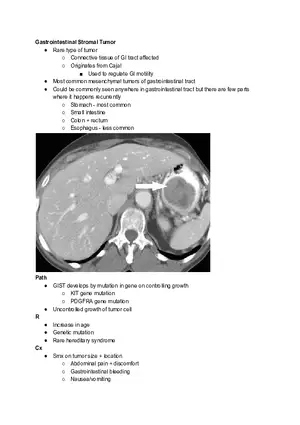

Gastrointestinal Stromal Tumor